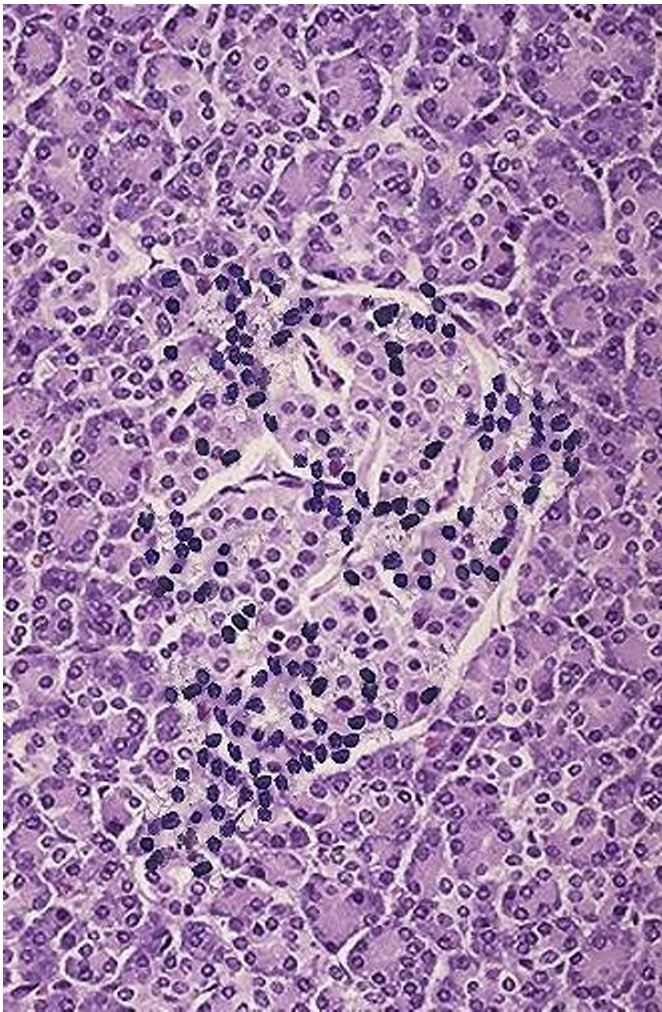

What condition is this from what disease

insulitis in T1D